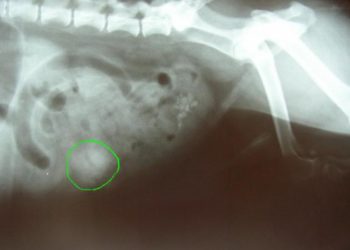

Comment soigner occlusion intestinale chat ? Selon l'avancement de l'occlusion, le traitement pourra être un changement d'alimentation ou une intervention ...